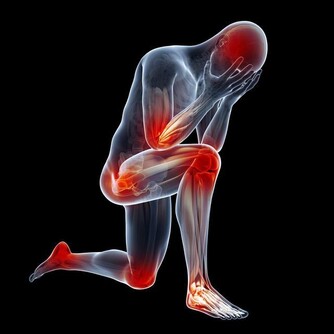

酒精對身體的危害十分廣泛包括心腦血管、中樞神經、消化系統、肝膽脾胃等,我下面著重介紹一下不大多見,與酒密切相關一種病,馬德龍病。